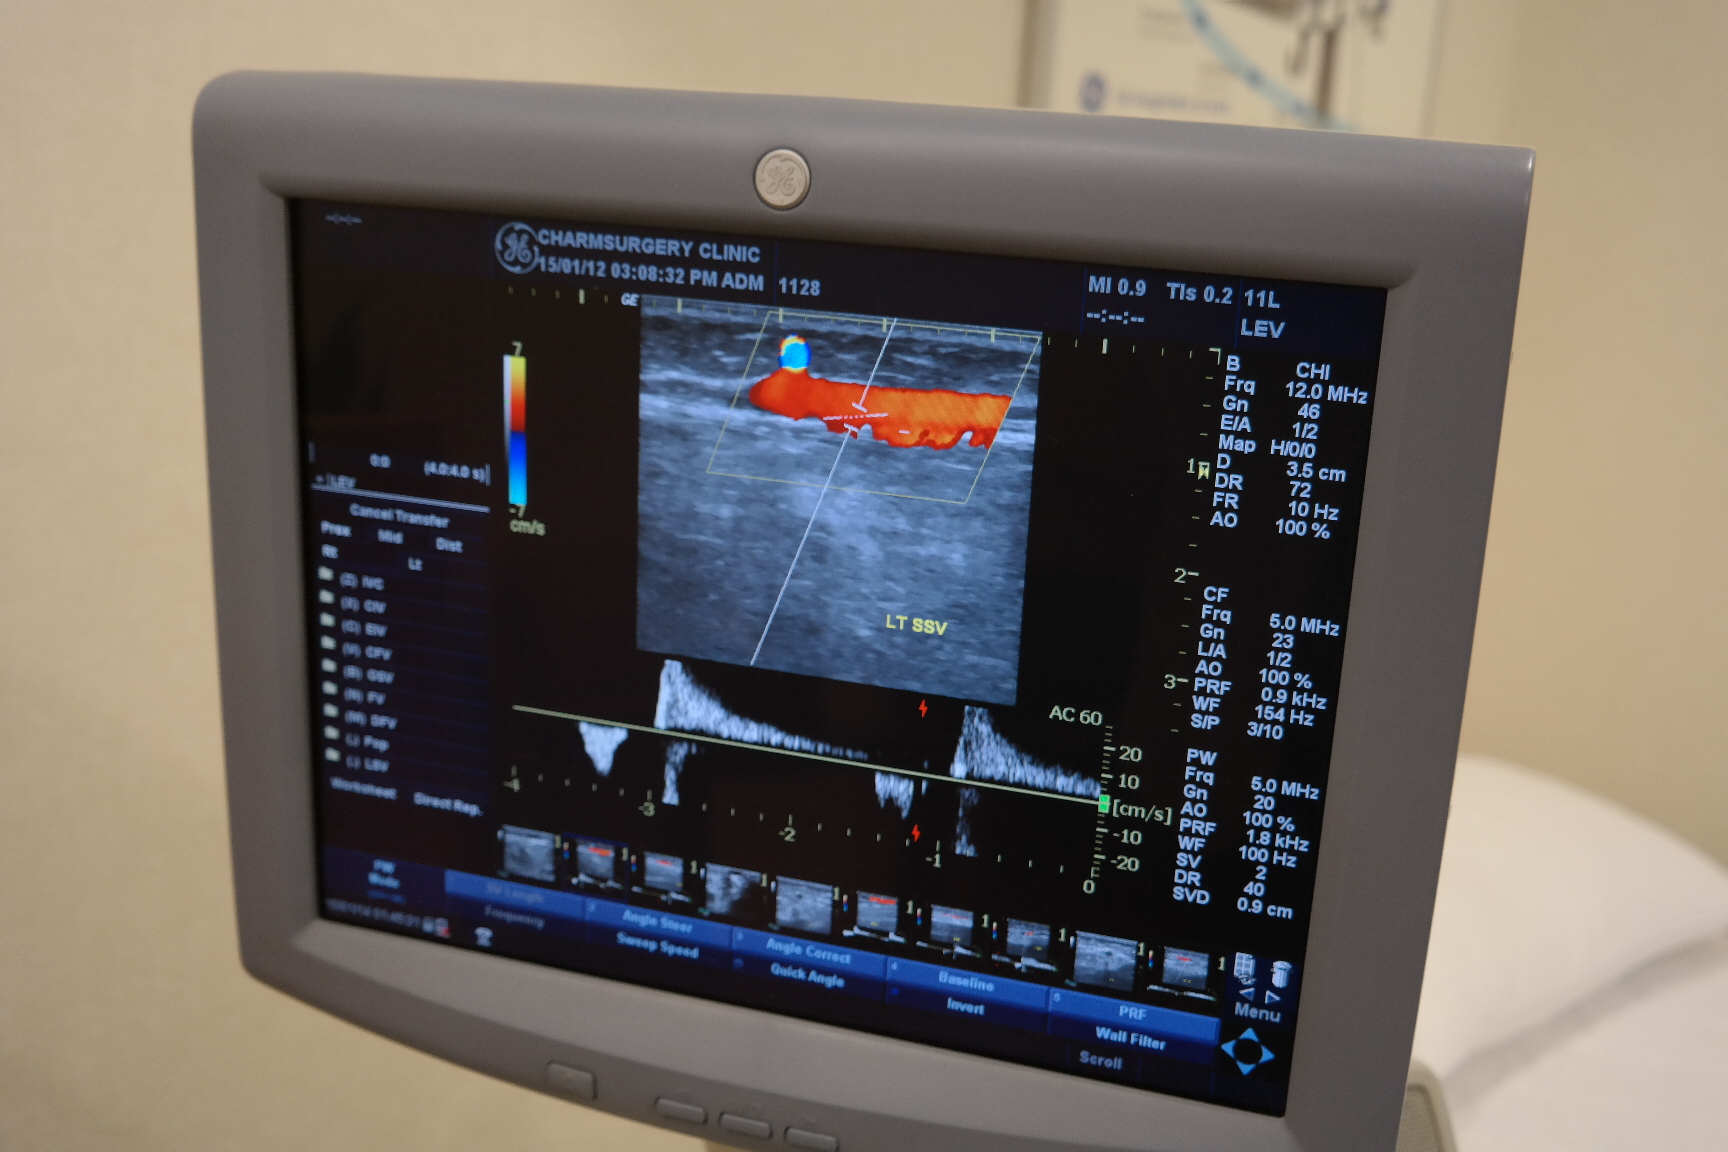

<혈관초음파상 역류가 관찰되는 소견>

중요한 것은 하지불안증후군 증상을 가진 환자에게 혈관초음파검사를 해보니 91%에서 만성하지정맥질환이 동반되어 있었다는 것이며 이중 68% 외관상 전혀 이상이 없었는데도 검사를 해보니 만성하지정맥질환이었다는 것입니다

즉, 외관상 울퉁불퉁한 하지정맥류 소견이 없었다 하더라도 하지불안증후군증상이 있는 경우에 만성하지정맥질환이 실제로는 잠재되어 있을 수 있다는 것이 결론입니다

거의 대부분의 경우에 혈관초음파 검사를 해보면 역류나 확장의 만성하지정맥질환에 해당되는 소견이 관찰됩니다